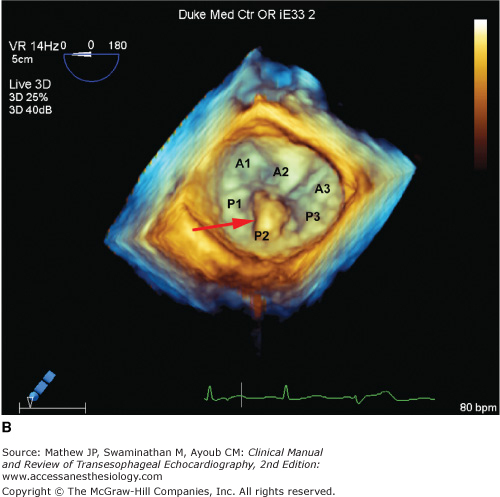

Two leaflets separated by two commissural areas cover the mitral valve area during systole. The anterior or aortic leaflet is situated anteriorly and to the right, adjacent to and in continuum with the aortic valve, and occupies approximately one-third of the annular circumference. Both the aortic and mitral valves contribute to the so-called fibrous skeleton of the heart, and the connection between the two is sometimes described as the aortomitral continuity. The posterior or mural leaflet occupies the remaining two-thirds of the annular circumference and is much narrower than the anterior leaflet. Although the posterior leaflet appears to have less height than the anterior leaflet, they are similar in surface area. The posterior leaflet is subdivided into three scallops by clefts. The scallop adjacent the anterolateral commissure is named P1, with P3 situated on the other end of the posterior leaflet in close relation to the posteromedial commissure. P2 is the middle scallop in between P1 and P3. Even though the anterior leaflet is not anatomically divided into scallops, the areas opposing the posterior leaflet are correspondingly referred to as the A1, A2, and A3 segments (Figure 7–1).5 Closure of the valve requires apposition and coaptation of the two leaflets, and this occurs along a single semilunar coaptation line. The ends of this coaptation line do not extend all the way to the annulus and are known as commissures. These commissural areas are situated anterolaterally and posteromedially, in relation to their papillary muscles.

Figure 7-1.

This full-volume 3D dataset of the heart demonstrates the mitral valve during diastole. The anterior leaflet, scallops of the posterior leaflet (P1, P2, P3), and both anterolateral and posteromedial commissures are clearly visible. (AOV, aortic valve; LAA, left atrial appendage; ALC, anterolateral commissure; PMC, posteromedial commissure; AML, anterior mitral leaflet.)